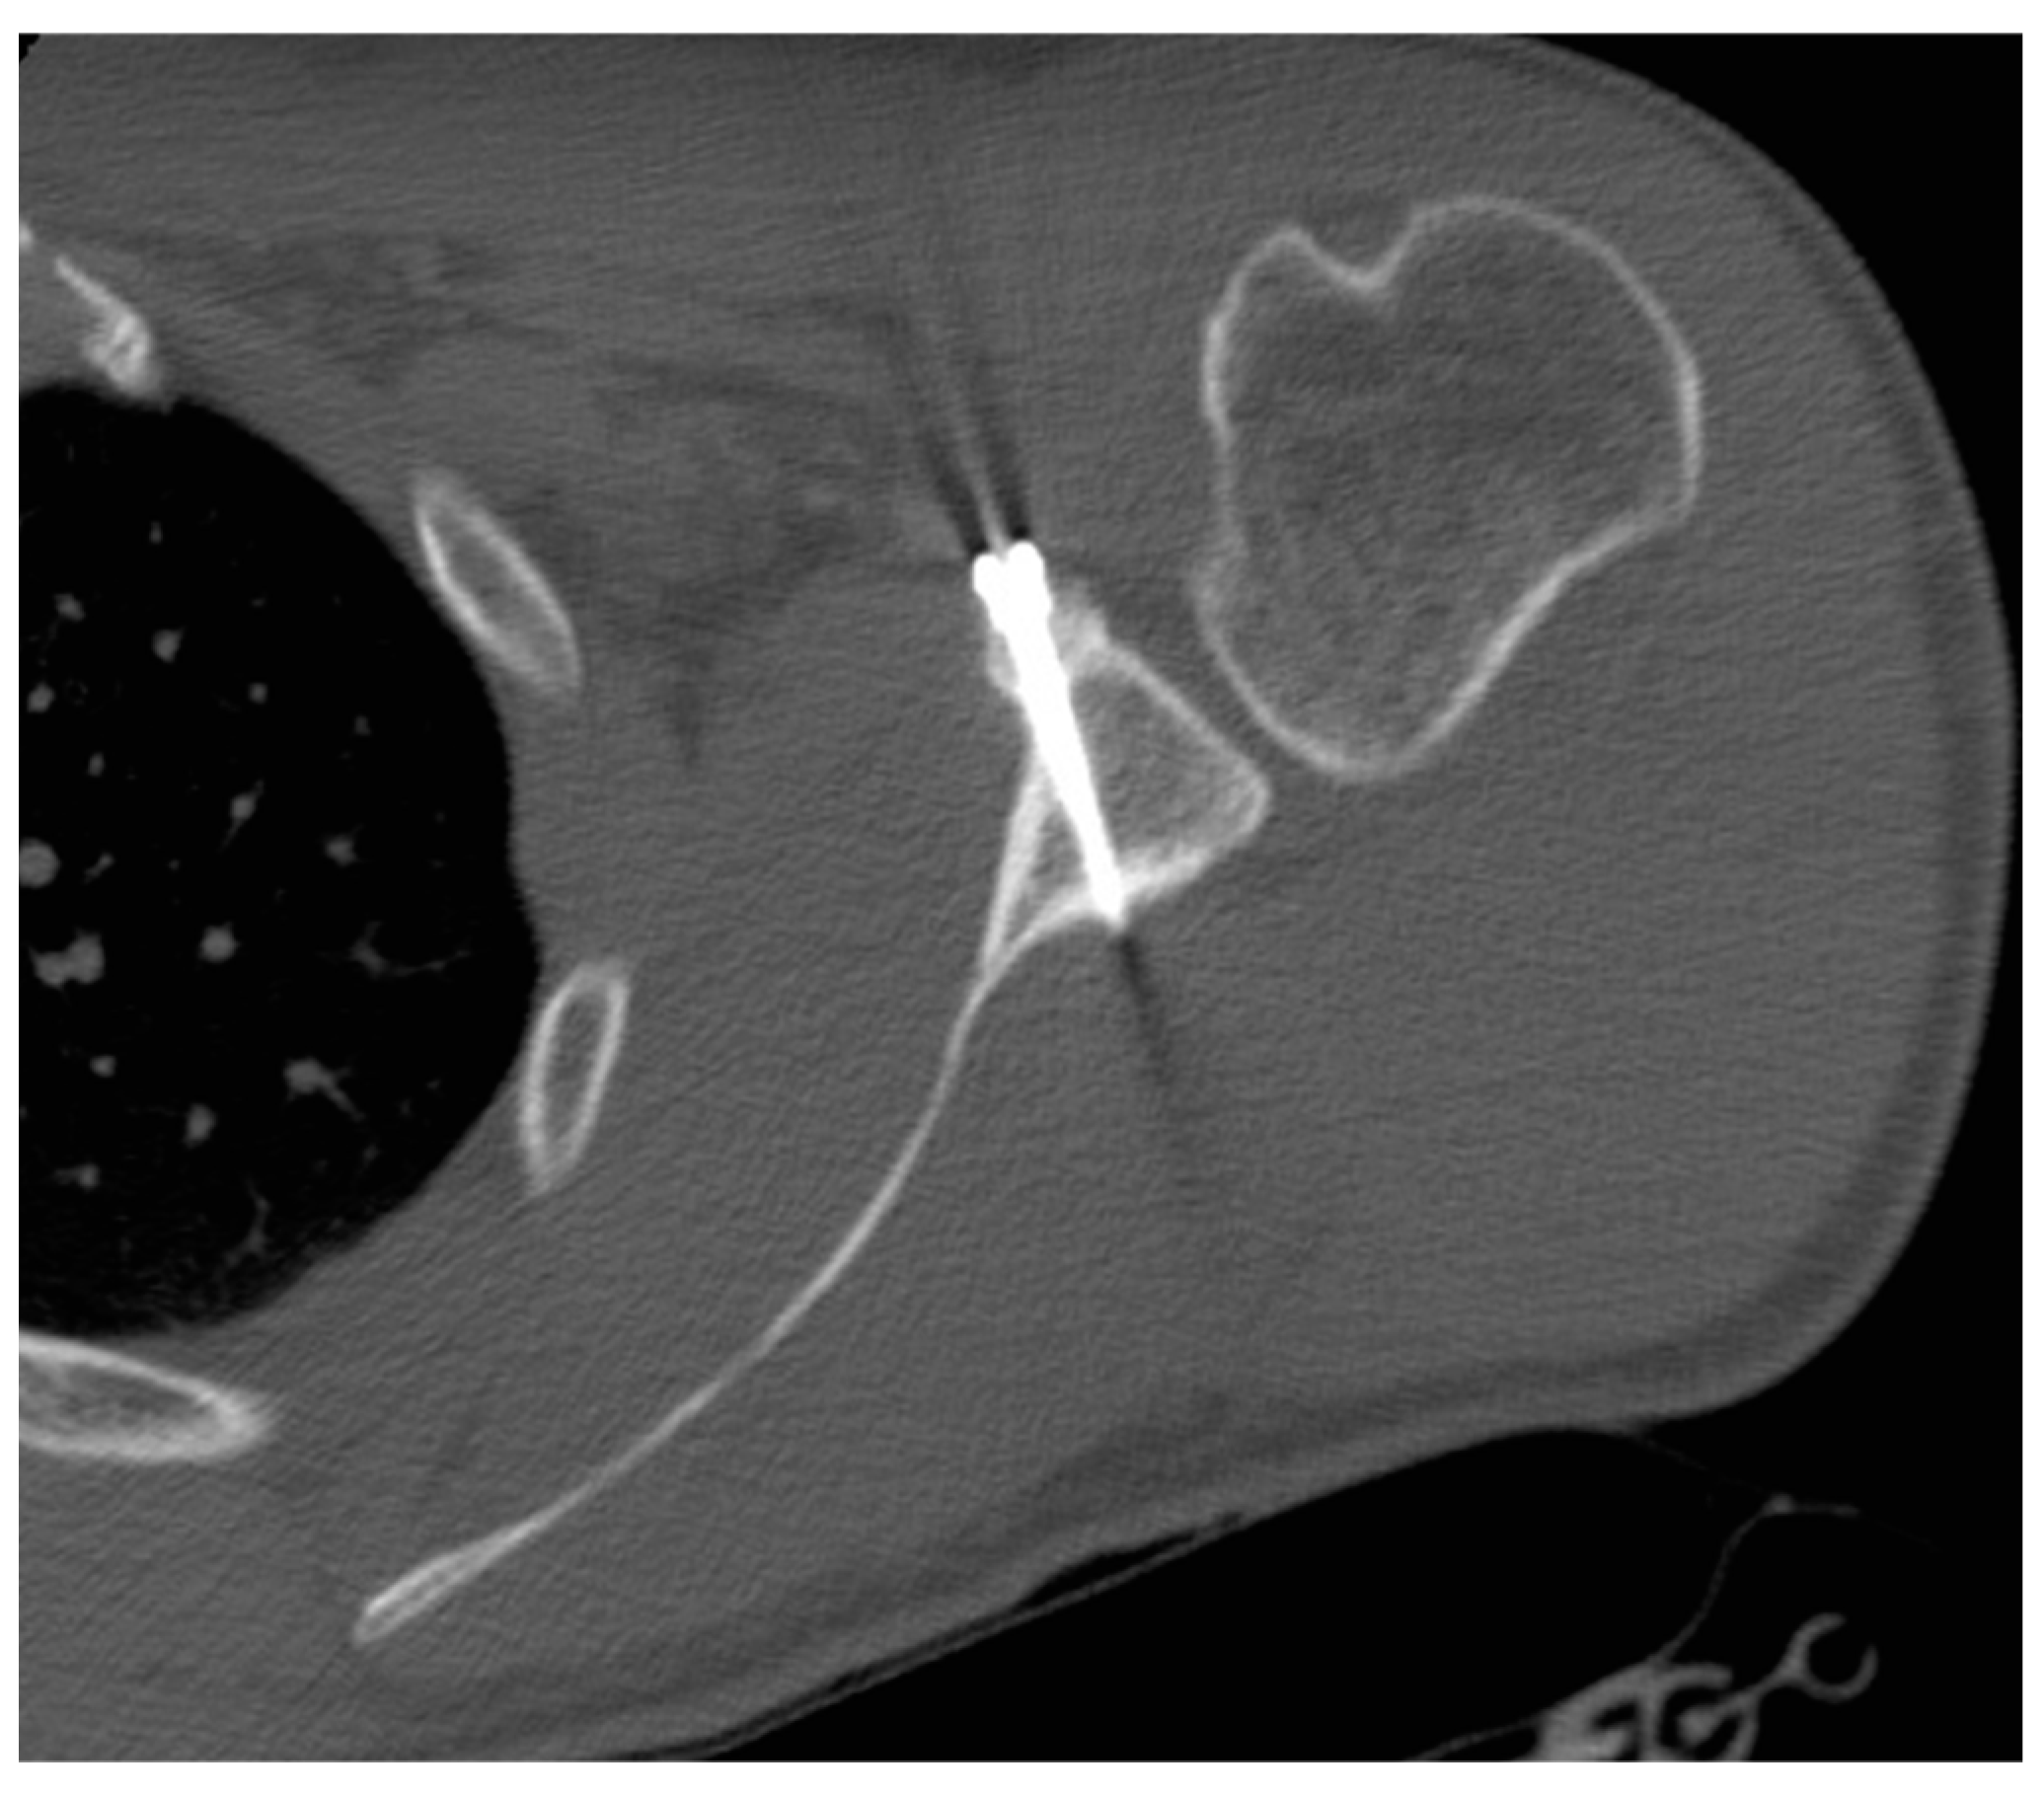

- The pectoralis minor was released, and a fresh portal was established with a needle over the coracoid, to insert the drill holes, at the junction of the lateral 2/3 and the medial 1/3. Two Kirschner wires through the coracoid were passed. The drill guide was removed. The holes were tapped, and the top hats were inserted into the fragment using a flexible Chia wire. The osteotomy was completed (Figure 2). The bone fragment was secured thought a coracoid screw passed over the Chia wire, using a double cannula.

- The graft was positioned on the anterior glenoid neck with the switching stick through the posterior portal (Figure 3).

- The graft was fixed. Two holes were made through the coracoid and the glenoid using the double cannula. Graft trimming was performed with the burr (Figure 4).